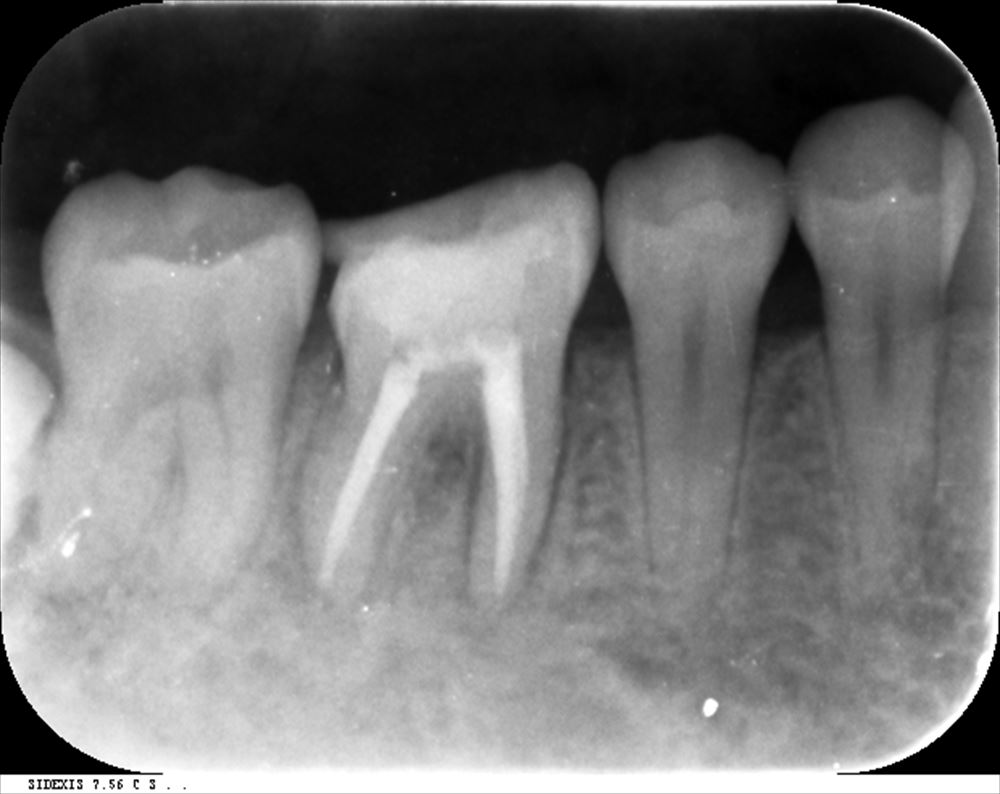

他院でリーマー破折。器具が残っています。

CTでも確認 ML根

取れました!!今日根管充填。症状もないです。

後ろのインプラントは私が去年埋入。同時に上部を作っていけそうです。歯の保存をまず考えています。